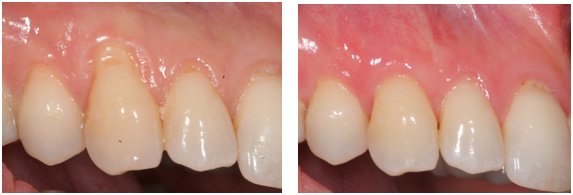

About Michael Wasemiller, DDS Creating Healthy Smiles One Patient at a Time. Dr. Wasemiller specializes in dental implants and periodontal procedures along with advanced minimally invasive sinus lift techniques. Periodontics is the field of dentistry that focuses on the area surrounding the teeth: the bone and gums. Your referring dentist focuses on the restoration of your teeth. Dr. Wasemiller works closely with your referring dentist... (Show more)